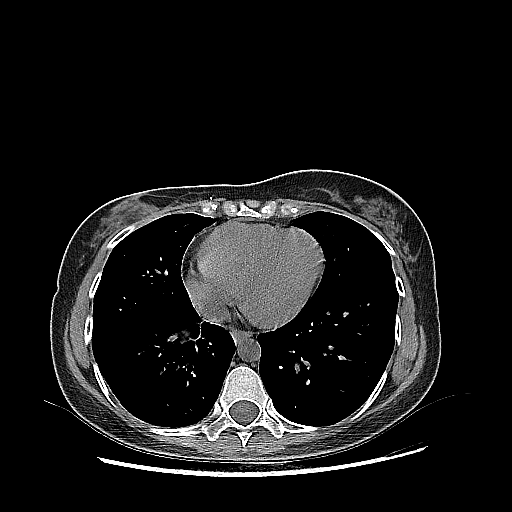

Reconstructed NATIVE CT scan (cycle consistency)

Full window (WL 1023.5, WW 4095 β†’ Low βˆ’1024, High +3071)

Actual HU range: [-1024.0, 722.3]